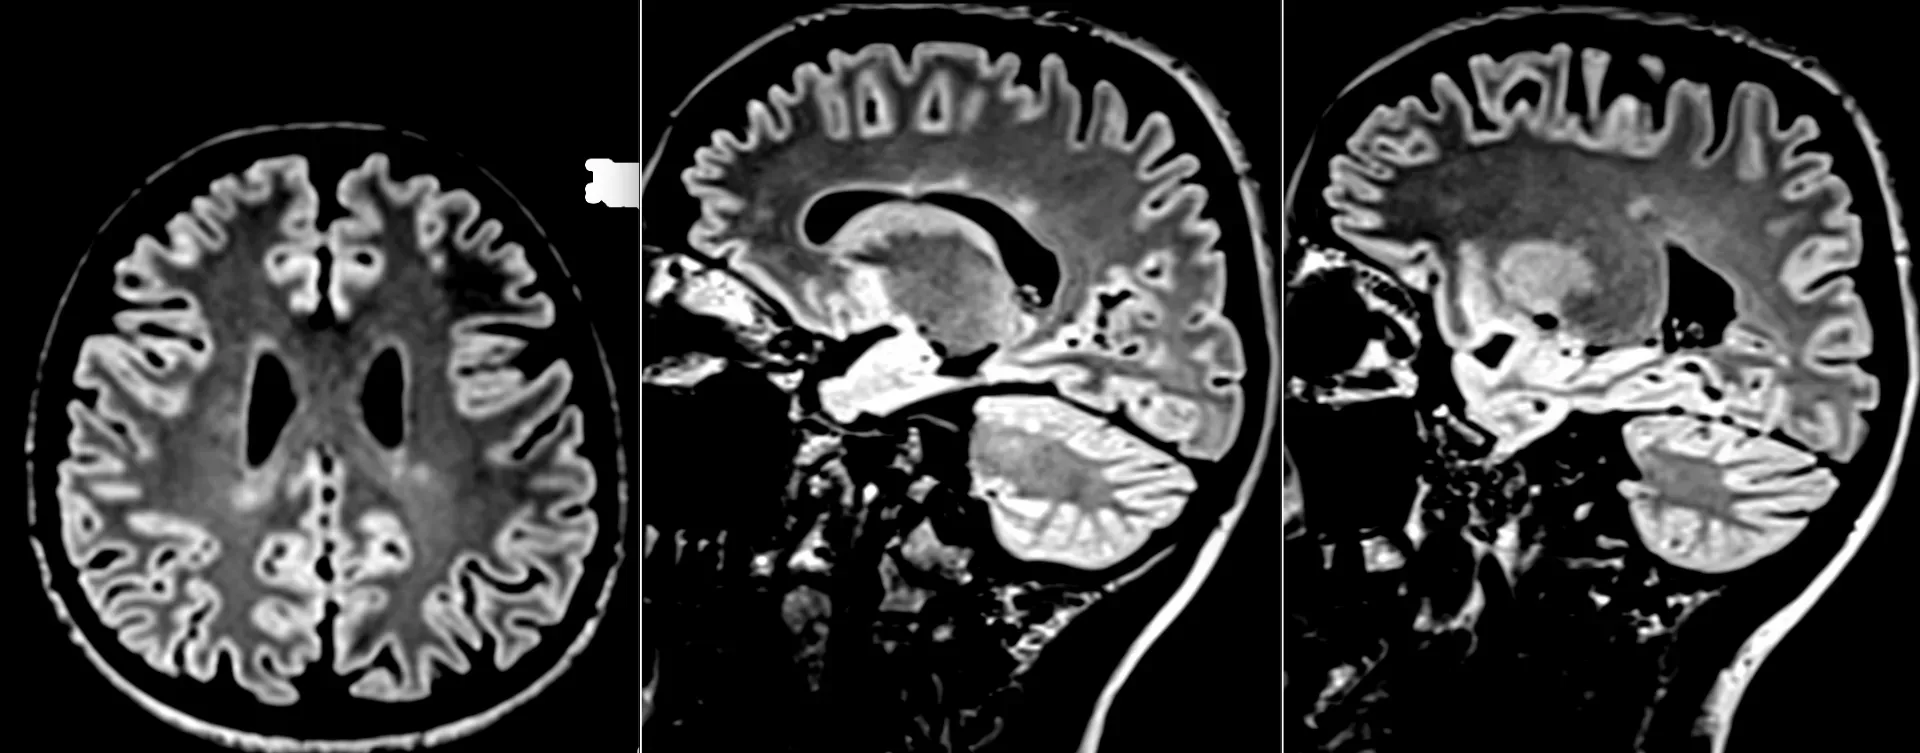

Клинический случай кавернозной мальформации, ассоциированной с венозной аномалией развития (ВАР). Следует напомнить, что ВАР часто сочетаются с каверномами, однако точные статистические данные не привожу, чтобы простимулировать самостоятельный поиск информации и закрепление знаний. Клиническая симптоматика у данного пациента отсутствует, что является типичным сценарием для подобных находок. Диагноз установлен случайно.